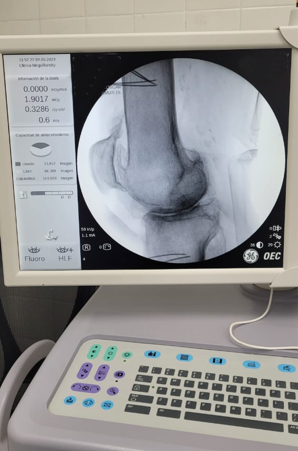

Paciente con dolor intenso por artrosis severa de rodilla

Candidato a un reemplazo total de rodilla, el paciente sentía un dolor tan intenso que le impedía la marcha.

Por la morbimortalidad de la cirugía, se procede a realizar en Tidol un tratamiento con radiofrecuencia, debido al dolor intenso que le impedía la marcha.